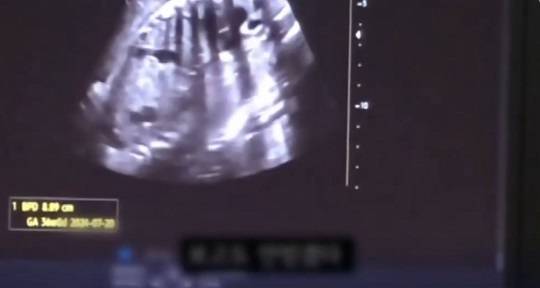

'36주 태아 낙태 사건'을 수사 중인 경찰이 수술을 집도한 의사가 따로 있었던 것을 확인하고, 해당 의사를 살인 혐의로 입건했습니다.